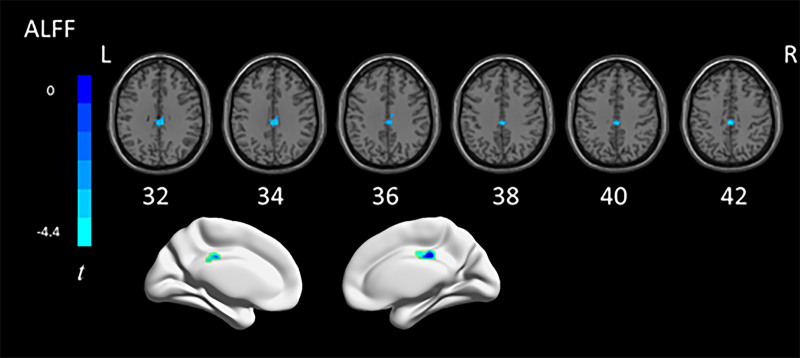

To date, most studies on autism spectrum disorder (ASD) have focused on specific age ranges, while the mechanisms underlying the entire developmental process of autism patients remain unclear. The aim of this study was to investigate the alterations in brain function in autistic individuals at different developmental stages by resting-state functional MRI (rs-fMRI). We obtained rs-fMRI data from 173 ASD and 178 typical development (TD) individuals in Autism Brain Imaging Data Exchange, spanning child, adolescent, and adult groups. We characterized local brain activity using the amplitude of low-frequency fluctuations (ALFFs), regional homogeneity (ReHo), dynamic ALFF (dALFF), and dynamic ReHo (dReHo) metrics. Pearson correlation analyses were conducted on relationships between Autism Diagnostic Observation Schedule scores and activity measures in abnormal brain regions. We found abnormal ALFF values in the medial and lateral orbitofrontal gyrus and right insula cortex with ASD compared with the TD group. In addition, compared with adolescents with ASD, we found that adults with ASD exhibited an increase in dReHo values in the posterior lateral frontal lobe. We also found that changes in ALFF were associated with the severity of autism. We found abnormal activity in multiple brain regions in individuals with autism and correlated it with clinical characteristics. Our results may provide some help for further exploring the age-related neurobiological mechanisms of ASD patients.